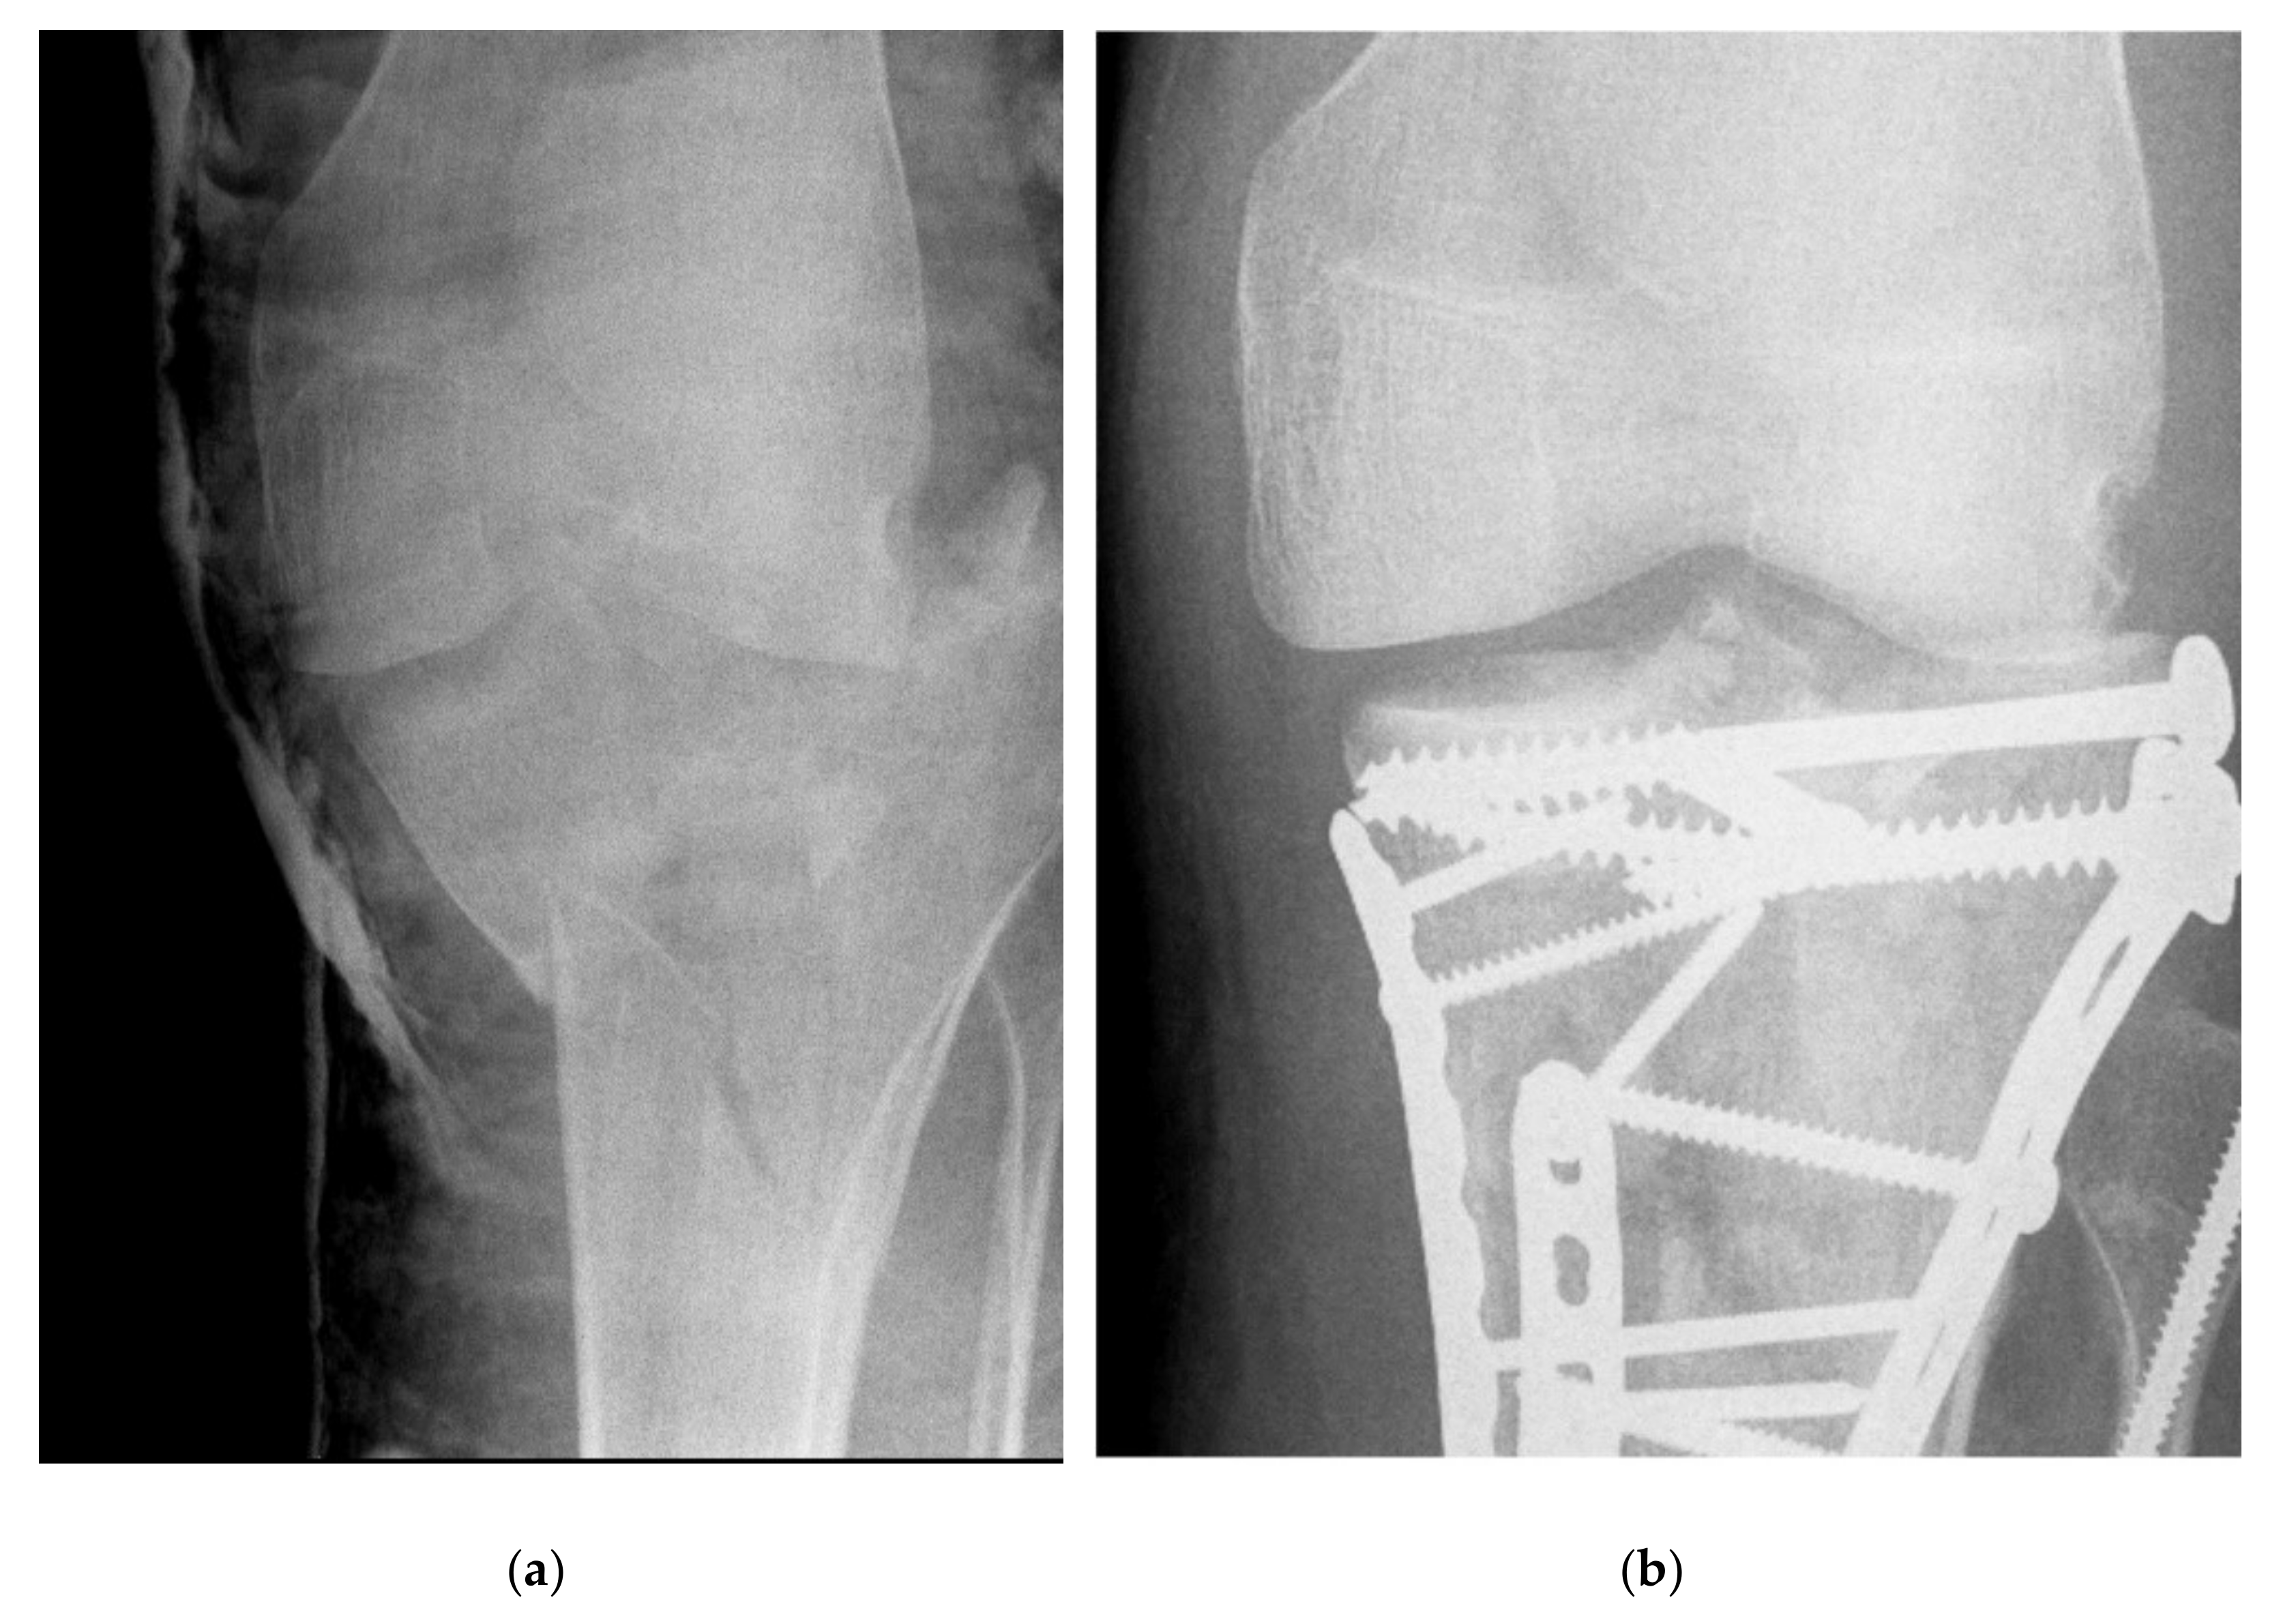

2.2. Radiographic Assessment